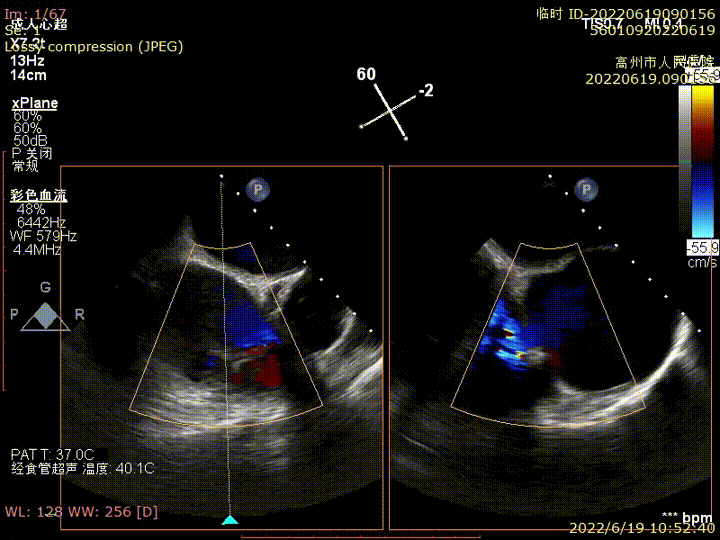

心脏彩超:三尖瓣关闭不全,收缩期可见极大量反流,VC>20mm,EROA:1.56cm²,反流峰速3.1m/g,压差33mmHg,三尖瓣反流5+。

术前TEE提示三尖瓣极重度反流

食管中段RV inflow-outflow引导前叶及隔叶分别捕获

术后超声显示反流基本消失